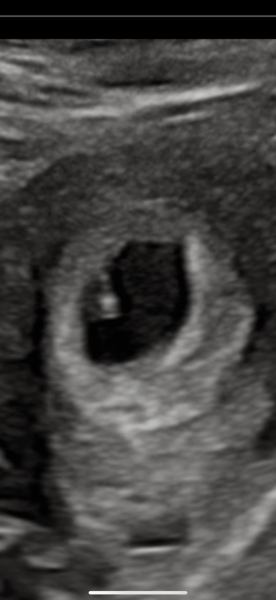

Little update for you. So I have a little bleed inside. But there is a heartbeat! 🥲

Bleeding has actually stopped today too. So that's great. Now I can breathe....

@pcbrb @TinyShrew17 all went well and growing faster than they expected and put me at nearly 7 weeks! Feeling absolutely petrified that I actually may have to give birth 😅

@greendot1 Awww congrats! Really good news and amazing to have a first picture of your tiny bean 😍✨✨✨ I'm really happy for you.. wish you that it keeps growing safely ♥️🫶🏼

They actually put me at less than I expected. But they didn't seem concerned. I guess it's kinda difficult to get a measurement on something so small this early on. I have another scan next Wednesday, so will be able to see difference hopefully